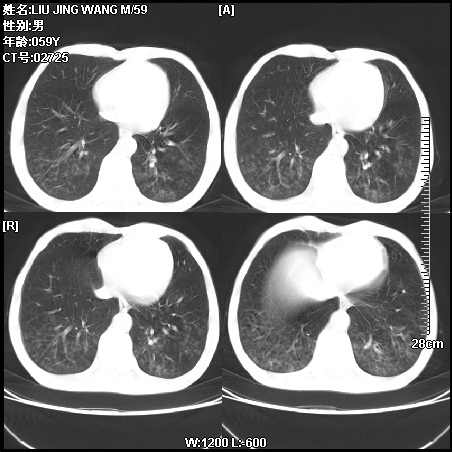

肿瘤科住院病人,都有食管癌史,都有放化疗治疗,两下肺病变是转移灶?还是其他原因造成?请老师指点

病例一 现呼吸困难,经抢救多次,咳嗽咳痰,发现食管癌2个多月

第一个病例我感觉不是转移,第二个是个放射性肺炎;但两个都有纵隔淋巴结肿大,以第二个为主;请楼主参考

符合放射性肺炎,第一例不除外坠积效应